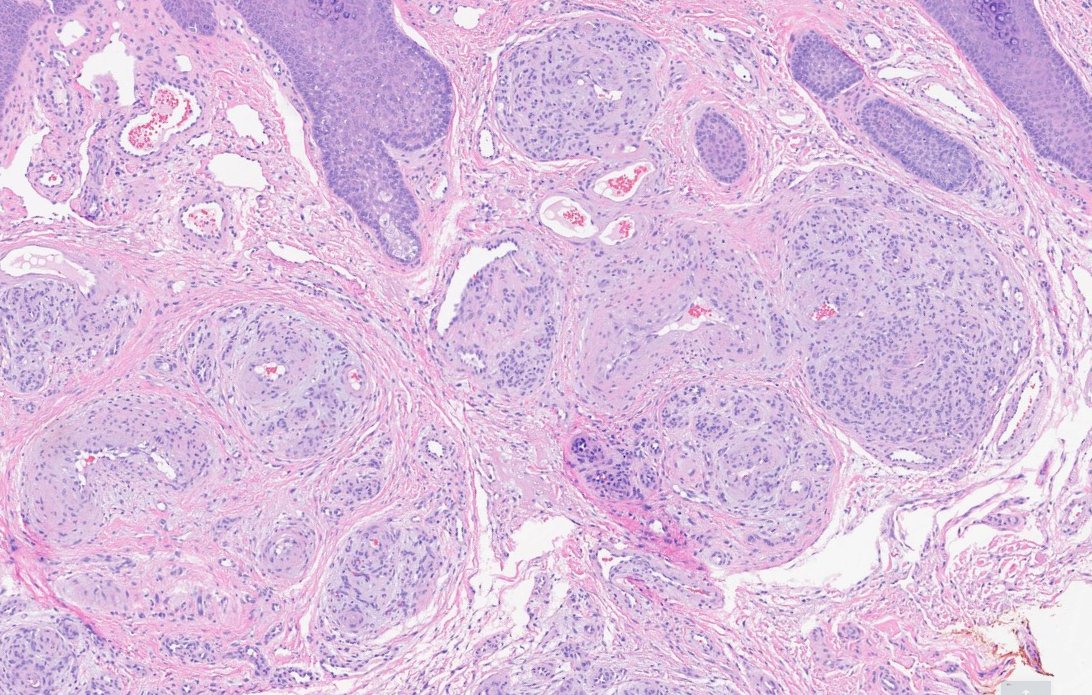

#dermpath 62 yo Man upper back. You worried about this โ€œnevusโ€ ? @david_terrano @et565 @DrGeeONE @SGottesmanMD @kis_lorand @HoustonArsenal @Dr_Jukic @glinglerimek @pembeoltulu @gonzadetoro stains are SOX10 and P16โ€ฆ